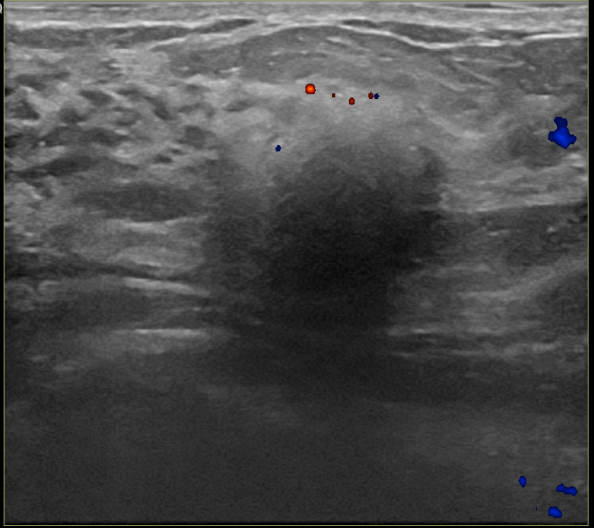

상기환자는 만져지는 멍울로  내원하신 30대후반

여성분으로 의심스러운 우측혹 조직검사 시행해 침윤성암으로 진단되었습니다